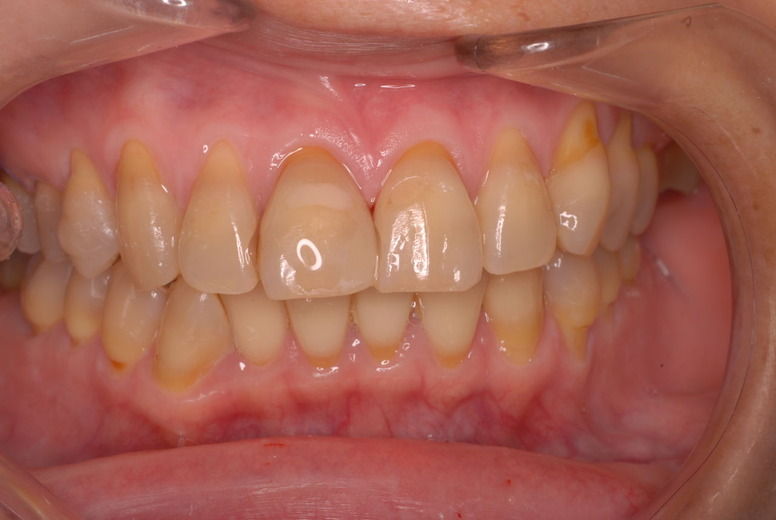

14年歯前、歯の神経が腐り、神経を除去したまま来なくなった現在大学生の女性

歯周病になっていましたが、少し色が黄色くなっているだけで比較的綺麗な歯の状態です。

平成9年来院神経を取り、同時に歯周病の話をしてそのまま来なくなっていたかたですが、たまたま一部欠けてきました。それで来院。